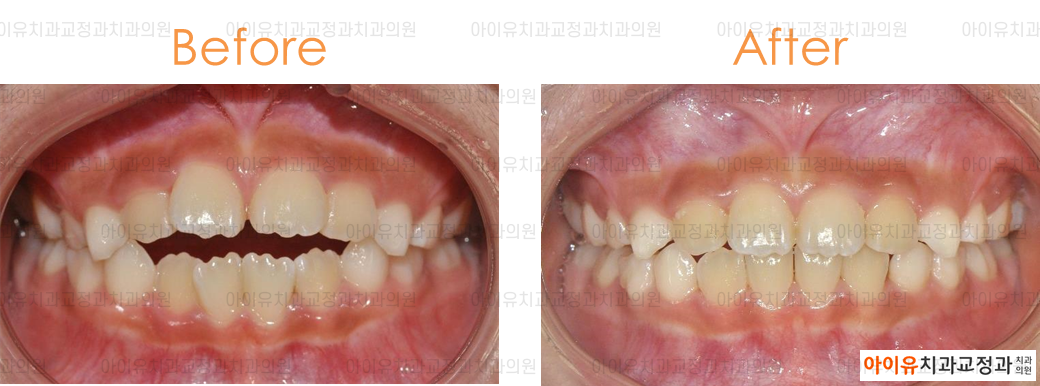

아래는 지난 몇 년간 울산 아이유치과에서 진행한 인비절라인 치료결과, 전후사진 중 일부입니다.

만7세 어린이 / 개방교합 / 치료기간 6개월 / 인비절라인 사용

위의 치료 결과에서 알 수 있듯 대부분의 경우에서 투명교정은 기존의 브라켓 교정과 동일한 효과를 얻을 수 있습니다.